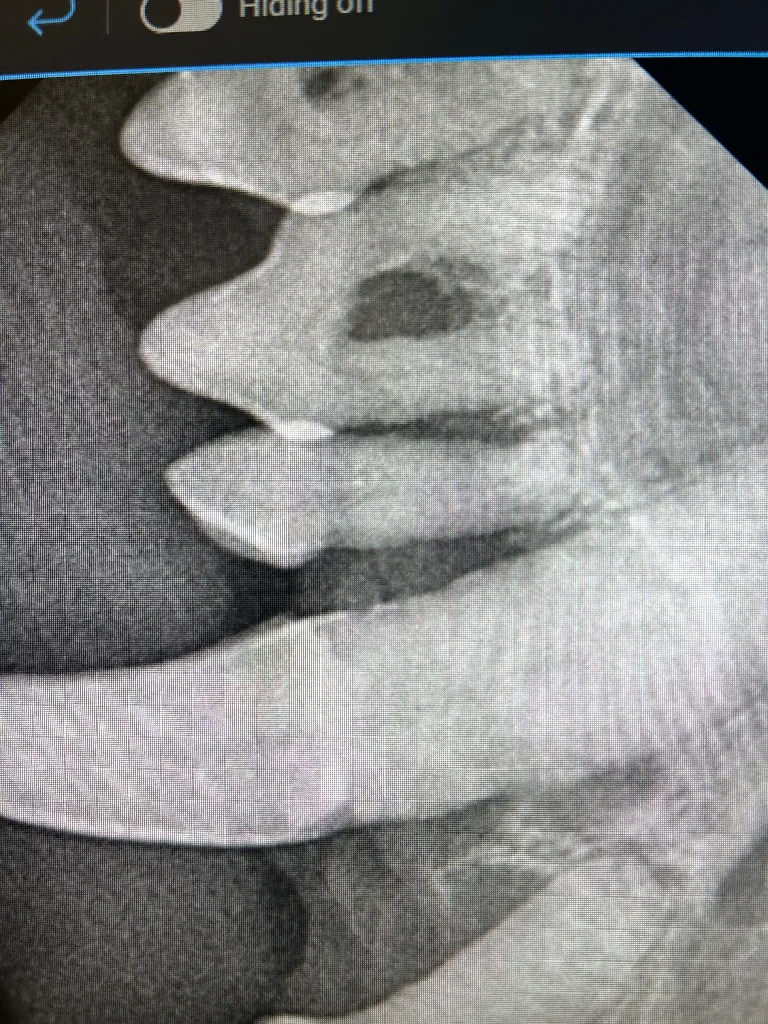

At Meadowmont Animal Hospital, we employ advanced digital radiology technology to swiftly and accurately diagnose your pet’s medical conditions. Digital radiology allows us to obtain detailed, high-resolution images of your pet’s internal structures quickly, minimizing stress and discomfort. These services are available for pets, ensuring comprehensive care for all species.

- Enhanced ability to diagnose fractures, internal abnormalities, and dental conditions